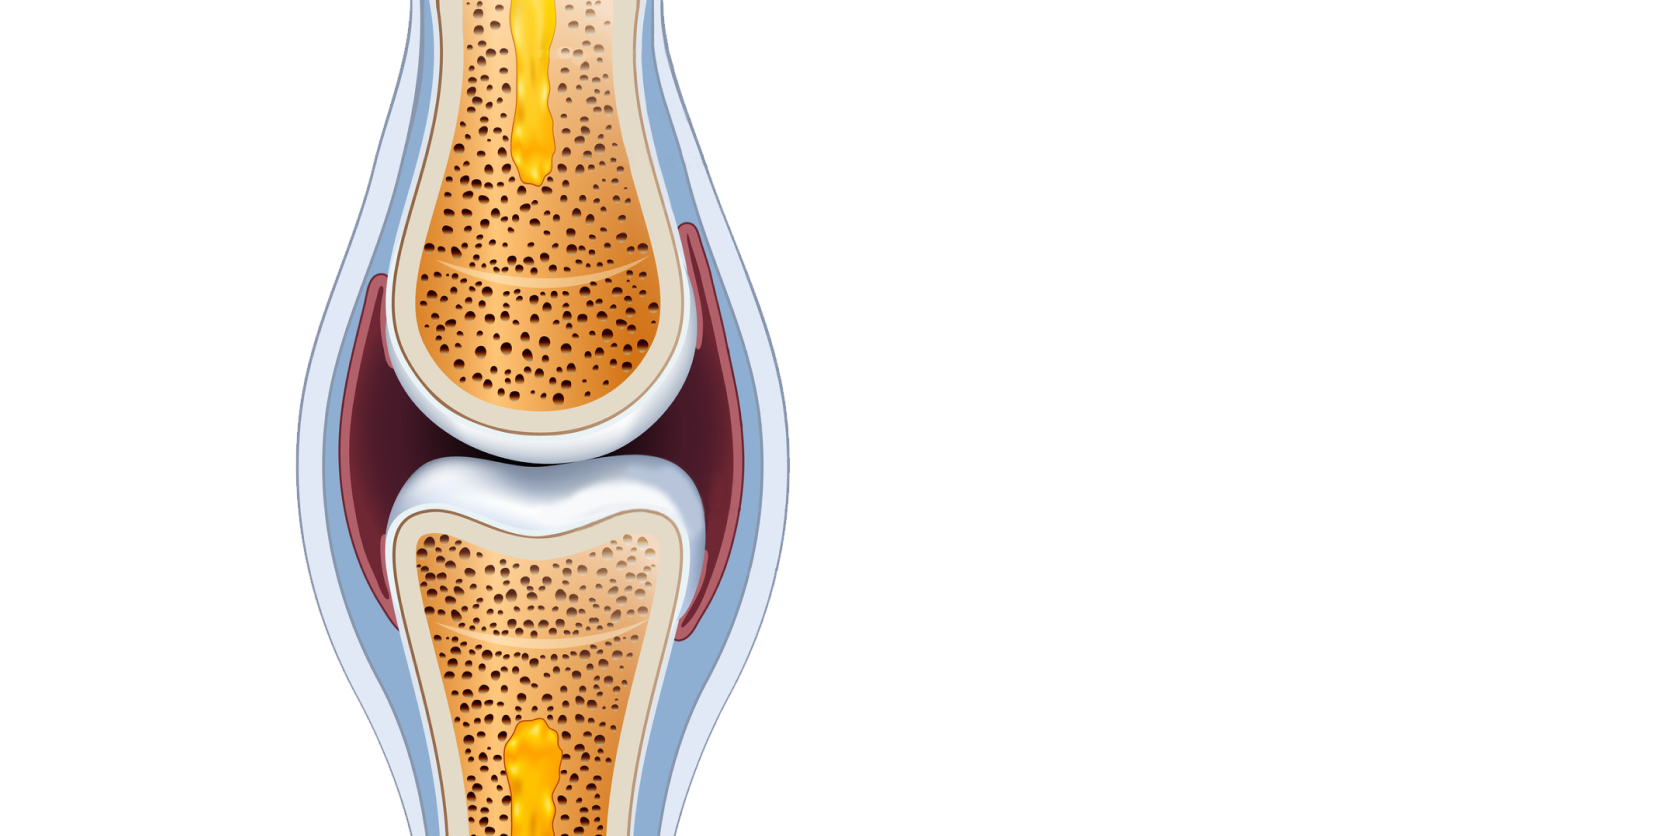

Хондроитина сульфат, гиалуроновая кислота, витамин Е, вспомогательные компоненты.